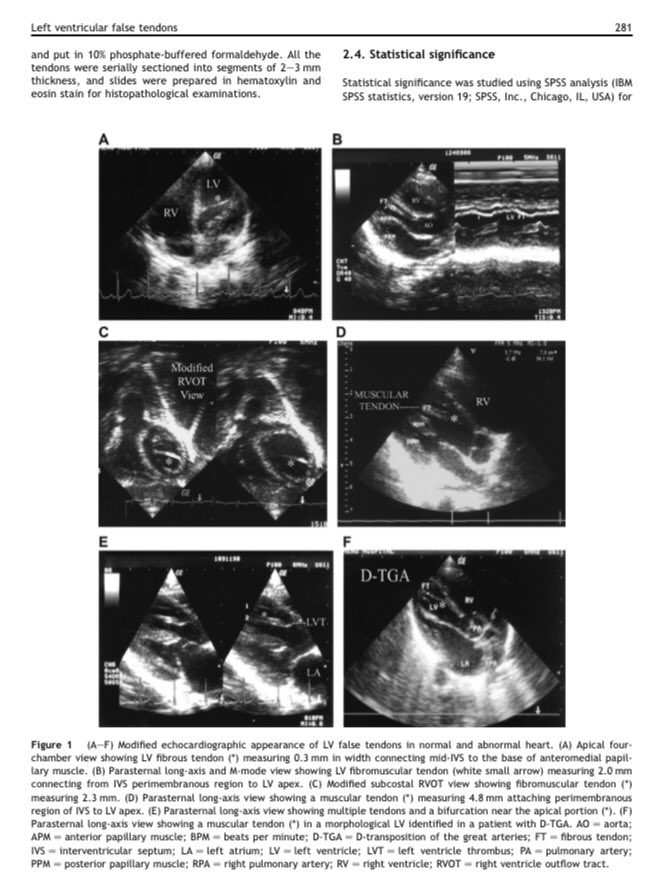

@MGibreel1 @AlkashkariWail @dromartamimi1 @mirvatalasnag @ctisus @Jazzminem2008 @blaorbla @WafaMussa @drzgezdentok1 @KemalogluOz @EchoAshwag @CyntiaMachain @TanMohammedMD @NunziaBorrell12 @rao_sruti @kirschj LV false tendon is a common finding in #CHD . 3 types:

-fibromuscular (must frequent)

-fibrous

-muscular (thicker)

They aren’t circumferential &, if they aren’t in the LVOT, they don’t cause obstruction.

There can be more than 1.

pediatr-neonatol.com/article/S1875-…